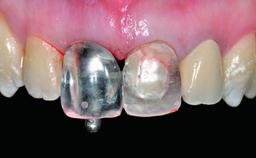

A healthy 37-year-old female patient was referred for a consultation on the replacement of missing tooth 21 with an implant-supported restoration. She stated that several years previously the tooth had been traumatically avulsed following a motor vehicle accident. The tooth was replaced with a three-unit fixed partial denture (FPD) immediately afterwards. Over time, she became disillusioned with the FPD and looked for a different option, including orthodontic therapy. She presented still in her orthodontic appliances, with the pontic sectioned free from the FPD but attached to the archwire. Her orthodontist felt that orthodontic treatment had been successfully completed, but nevertheless referred her before removing the appliances in case adjustments were necessary.

Retention Cemented, with prosthesis margin < 3mm submucosal Cemented, with prosthesis margin < 3mm submucosal

Provisional Implant-Supported Prosthesis Prosthodontic margin > 3 mm apical to mucosal margin Prosthodontic margin > 3 mm apical to mucosal margin

Interim Prosthesis during Healing Fixed Fixed